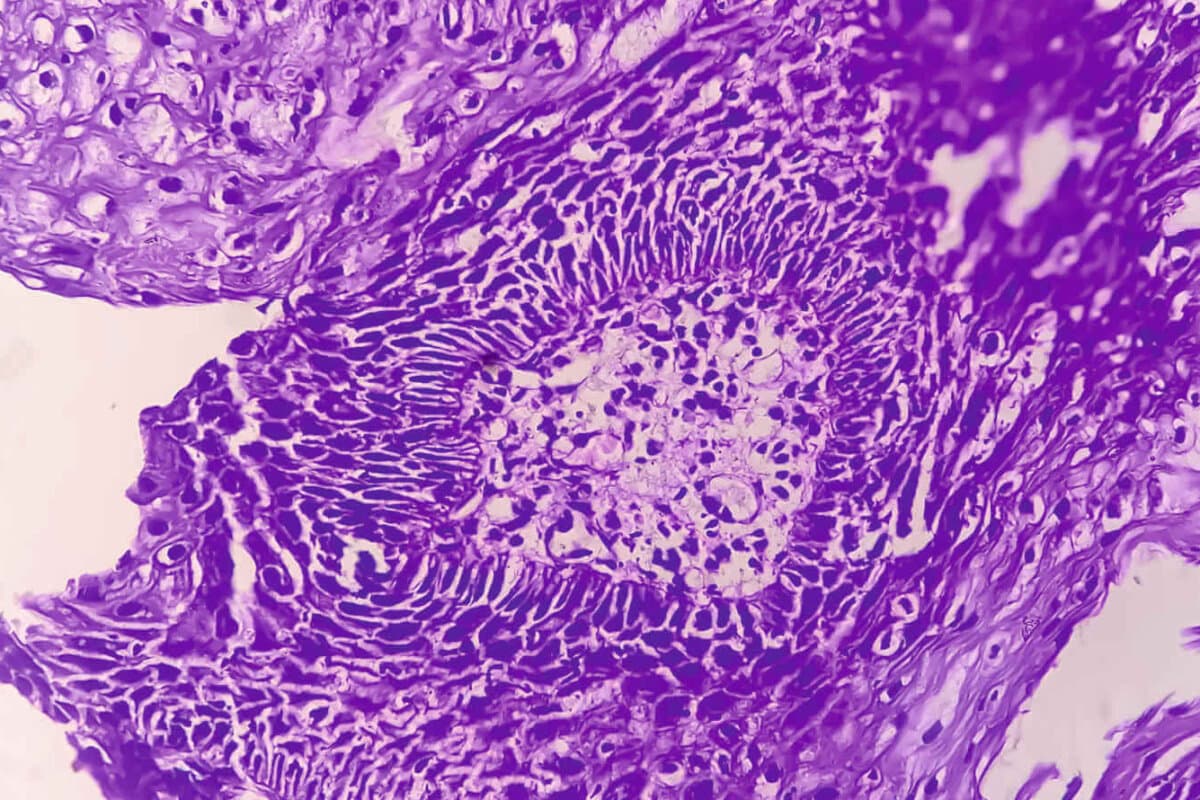

Rund 15% der Kolonkarzinome weisen einen Defekt der Mismatch-Reparatur (dMMR) auf. Bei ihnen sind mehrere Besonderheiten bekannt. Therapeutisch weisen sie etwa einerseits eine relative Resistenz gegenüber Chemotherapien auf, andererseits zeigen sie ein vergleichsweise gutes Ansprechen auf Immuntherapien. Ungeachtet dessen erhalten dMMR-Patienten im Stadium III weiterhin adjuvant die Standard-Chemotherapie mit Fluoropyrimidin plus Oxaliplatin.